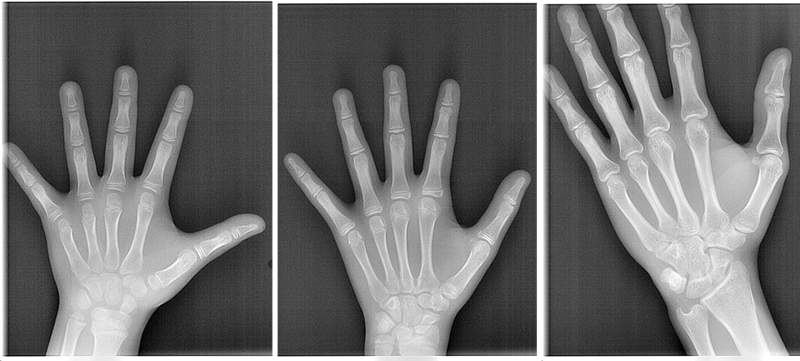

成長には個人差があるため、実際の年齢(歴齢)と骨格的な顎の成長の年齢(骨年齢)を把握する必要がありますが、簡便かつ有効な方法として手のレントゲンを参考にして、矯正治療の時期とタイミング、さらに適切な装置を考慮します。

手の全体のレントゲンを撮影し、主に中指(第三指)の関節と親指(第一指)の骨(種子骨)、手首の骨(橈骨)の分析を行うことで、成長期のお子さんの骨年齢を把握し、暦年齢と比較して成長のスパート時期を推測します。また、下顎の成長終了を予測して、小児矯正の終了時期や本格矯正(第Ⅱ期治療)の治療予測を立てるためにも有効な手段です。

この場合、顎の成長がまだ残っていて成長を利用する治療(小児矯正)ができるかどうか、手のレントゲンで検査します。